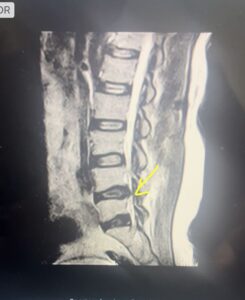

De acuerdo con la resonancia magnética, la hernia es de gran tamaño y comprime la raíz del nervio ciático en la extremidad inferior derecha que toca la médula, razón por la cual, se requiere de una intervención quirúrgica para corregir la sintomatología con un espaciador U de titanio, que le ayudará a recuperar su salud.